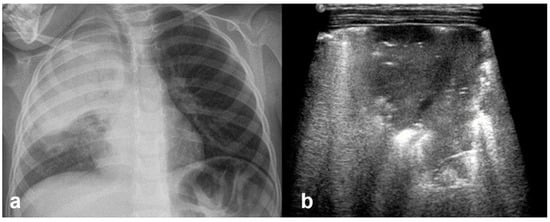

In RDS, lung ultrasound findings include consolidation or bilateral “white lung”, aero bronchograms, pleural line abnormalities, and the absence of A-lines (Figure 12, Figure 13, Figure 14 and Figure 15) [30,35,40,41].

Severe RDS shown on chest X-ray (a); LUS (b). The ability of the LUS to characterize the severity of the RDS is debatable.

RDS is a common cause of neonatal respiratory failure, particularly in preterm infants, resulting from surfactant deficiency and alveolar collapse. LUS has become a valuable diagnostic tool for RDS, offering real-time visualization of lung pathology at the bedside [38,42,43,44,45]. A hallmark sonographic feature of RDS is the presence of dense, confluent B-lines throughout the lung fields, producing a “white lung” appearance due to the loss of normal aeration. Notably, the whole lung is typically involved, with a diffuse, bilateral distribution that distinguishes RDS from more localized pulmonary conditions [37,46,47]. Additionally, interspersed consolidations may be present, including hypoechoic and subpleural areas of alveolar collapse, reflecting regions of complete de-aeration. These consolidations often lack air bronchograms and are associated with irregular or thickened pleural lines. The combination of diffuse B-line patterns, global lung involvement, and patchy consolidations provides a highly suggestive ultrasound profile of RDS and facilitates early diagnosis. In addition, for RDS, LUS may be used for severity assessment and the monitoring of treatment response in the neonatal intensive care setting [16,20,27,29]. The ability of the LUS to characterize the severity of the RDS is debatable (Figure 14 and Figure 16) [48].

Figure 16.

Interstitial emphysema shown on chest x-ray (a) and LUS (b). This case underlines the superiority of CXR in differentiating this pathology from RDS, which has a similar LUS appearance.